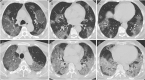

Materials and methods: A total of 102 patients with COVID-19 confirmed by a positive result from real-time reverse transcription polymerase chain reaction on throat swabs who underwent chest CT (53 men and 49 women, 15-79 years old, 84 cases with mild and 18 cases with severe disease) were included in the study. The CT-SS was defined by summing up individual scores from 20 lung regions; scores of 0, 1, and 2 were respectively assigned for each region if parenchymal opacification involved 0%, less than 50%, or equal to or more than 50% of each region (theoretic range of CT-SS from 0 to 40). The clinical and laboratory data were collected, and patients were clinically subdivided according to disease severity according to the Chinese National Health Commission guidelines.

Results: The posterior segment of upper lobe (left, 68 of 102; right, 68 of 102), superior segment of lower lobe (left, 79 of 102; right, 79 of 102), lateral basal segment (left, 79 of 102; right, 70 of 102), and posterior basal segment of lower lobe (left, 81 of 102; right, 83 of 102) were the most frequently involved sites in COVID-19. Lung opacification mainly involved the lower lobes, in comparison with middle-upper lobes. No significant differences in distribution of the disease were seen between right and left lungs. The individual scores in each lung and the total CT-SS were higher in severe COVID-19 when compared with mild cases (P < .05). The optimal CT-SS threshold for identifying severe COVID-19 was 19.5 (area under curve = 0.892), with 83.3% sensitivity and 94% specificity.